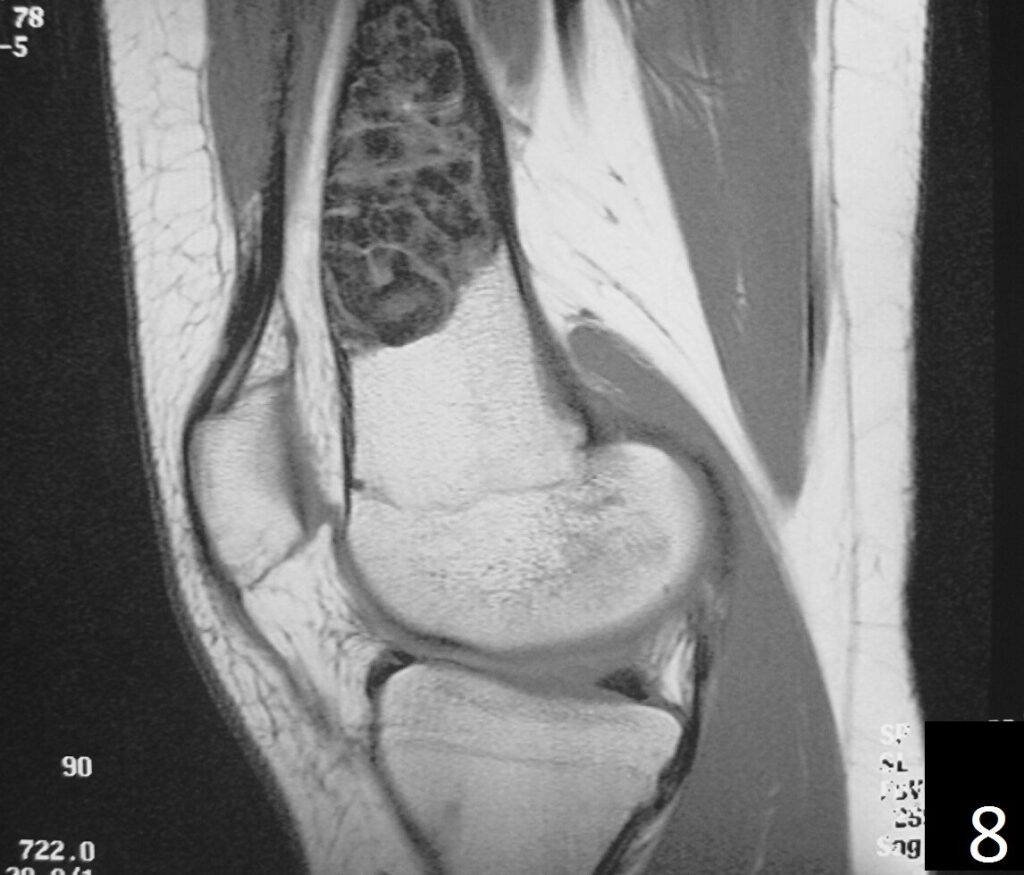

MRI

• Low- signal on T1 (Fig. 8)

• Variable heterogeneneous signal on T2 (Fig. 9).

• Possible extensive hypercellular fibrous tissue and hemosiderin seen on T2

• Can be useful for demonstrating an aneurysmal bone cyst component

Fig. 6-9: Sagittal T1 (Fig. 6) and T2 (Fig. 7) MRI of the knee demonstrates a fibrous cortical defect. Axial T1W (Fig. 8) and T2W (Fig. 9) show a heterogeneous lesion on distal femur, compatible with nonossifying fibroma.